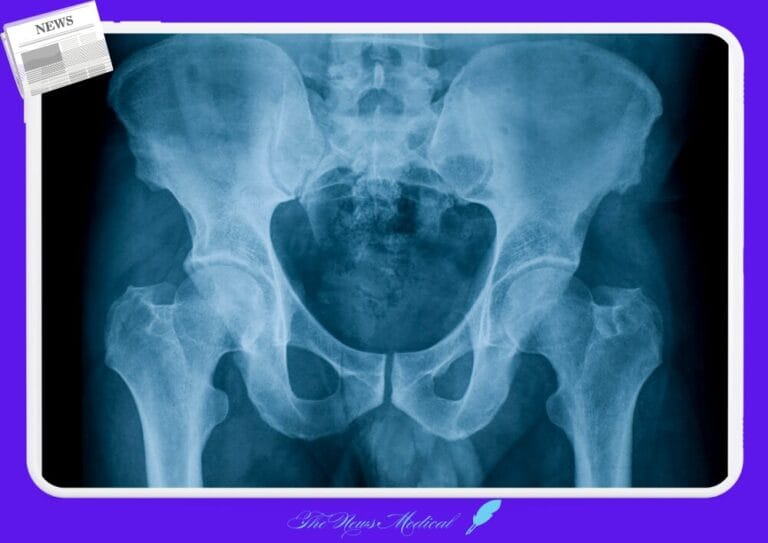

한의사 X-ray 사용 논란, 법원 판결과 의료계 반발 속 쟁점 부상 골반남자 엑스레이 방사선

한의사 X-ray 사용 논란, 법원 판결과 의료계 반발 속 쟁점 부상

한의사 X-ray 사용 논란, 법원 판결에 따라 한의사 X-ray 사용 가능?, 정부 지침과 의료계 반발로 논란 가열...